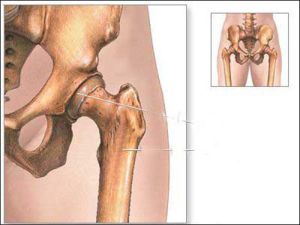

股骨頭就是支撐身體上半部分的兩根骨頭,具體位置在骨盆下方。股骨是人體最重要的骨骼,股骨頭更為重要,人的直立行走、活動、勞動都依靠股骨頭的支撐作用。

股骨頭股骨頭壞死

外傷導致股骨頭壞死的原因在於供應股骨頭的血管受損所致,如側方骨骺血管受損。這些血管受損後,股骨頭全部或部分失去血運

股骨頭壞死有報告稱,在粗隆間骨折穿針後也有股骨頭缺血壞死發生,這是由於股骨頭穿針所致,因為在穿針過程中可能傷及外側骨骺血管(穿針由股骨頭側上方或後方進入股骨頭)。這個血管的損傷可造成股骨頭局部缺血壞死,最後在股骨頭上部負重部位發生塌陷。另外,有時對髖部的直接打擊也會造成股骨頭缺血性壞死,急性髖關節脫位也可以造成股骨頭缺血性壞死。